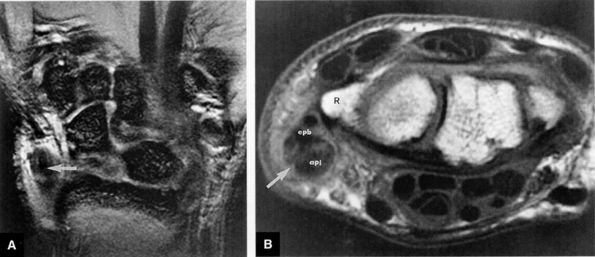

FIGURE 10.92 ● The scapholunate ligament forms a C-shaped complex, which is open distally at the level of the midcarpal joint. The membranous or proximal component forms the base of this C-shaped complex. The dorsal radiocarpal joint capsule inserts proximally into the dorsal component. The proximal aspect of the dorsal and volar components merges with the membranous component. Volarly, the radioscapholunate ligament inserts at the junction of the volar and membranous components of the scapholunate ligament.

|

![]() |

FIGURE 10.93 ● Dorsal fiber disruption of the scapholunate ligament on color illustration (A) and coronal FS PD FSE image (B). Tearing of the strong dorsal fibers is frequently associated with either degeneration or tears of the membranous component. (C) Normal dorsal scapholunate ligament fibers shown for comparison.

FIGURE 10.94 ● Coronal FS PD FSE images showing complete disruption of the volar (A), membranous (B), and dorsal (C) components of the scapholunate (SL) ligament. (D) A corresponding axial T1-weighted arthrogram demonstrates lack of scapholunate ligament fibers from the dorsal to volar aspects of the interval.